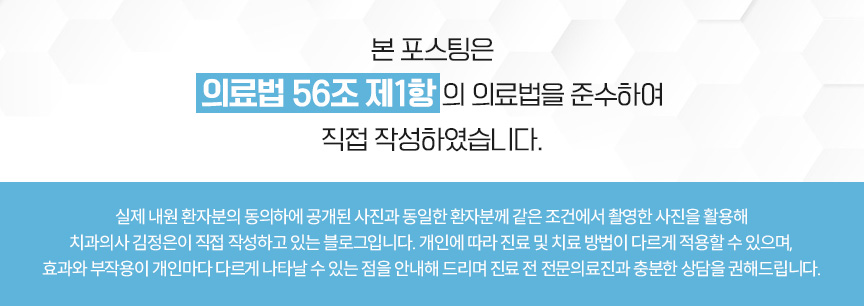

아래 사진은 면목역 치과 에서

촬영 한 사진 입니다.

가상의 선을 보면, 얼굴과 치열의

불균형이 있다는 것을 보여줍니다.

이런 경우, 심리적 위축 및 컴플렉스

까지 이어질 수 있습니다.

가운데를 기준으로 웃을 때 오른쪽으로

입꼬리가 높게 기울어져 올라간 것을

확인할 수 있습니다.

특별한 돌출 소견은 진단되지 않았지만

골격성 1급 부정교합으로 진단해

이어서 육안 검진을 이어갑니다.